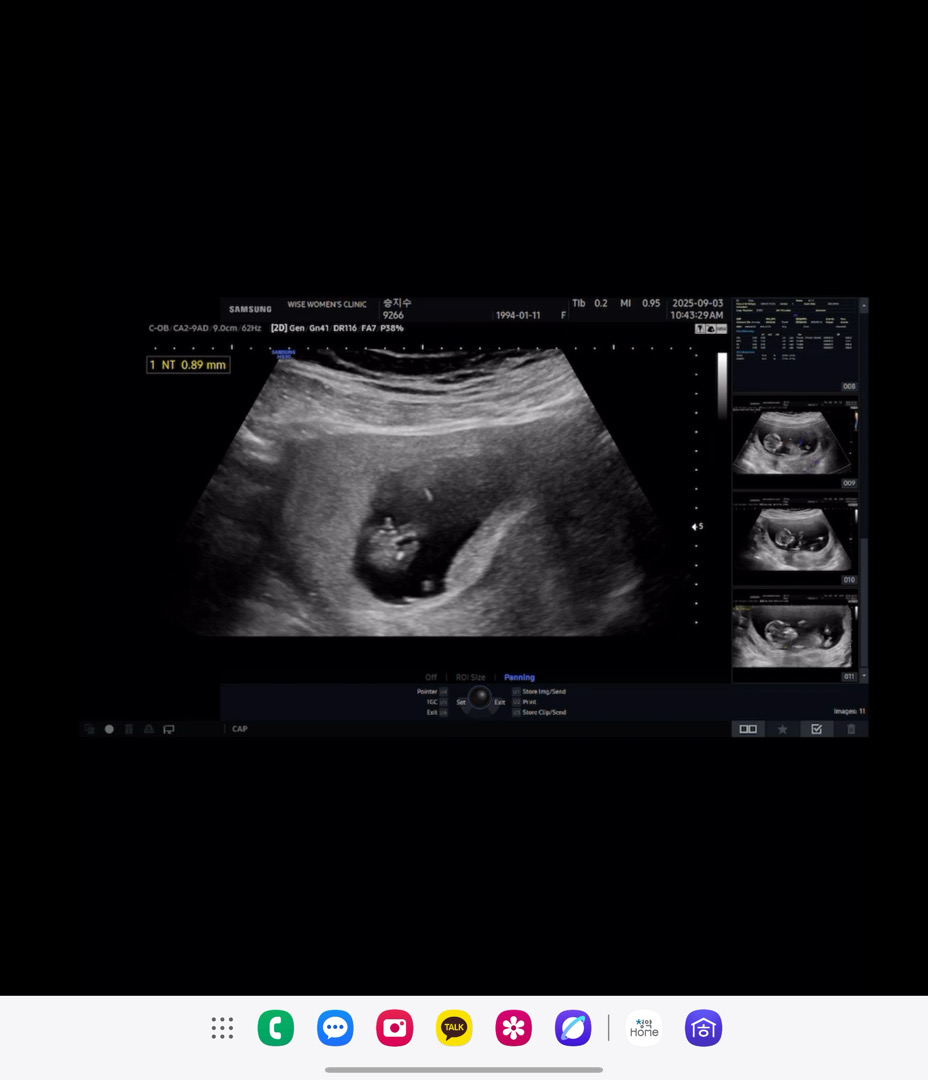

12주 고추가 이리 크게보이나요..ㅠㅠ

12주3일인데 의사쌤은 여자아이도 이땐 튀어나와있다고 아들확신 못한다고하시는데.. 고추같아서요ㅠㅠ